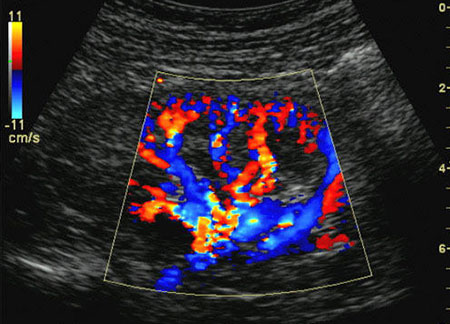

• Color Doppler : This type of Doppler uses a computer to change sound waves into different colors. These colors show the speed and direction of blood flow in real time.